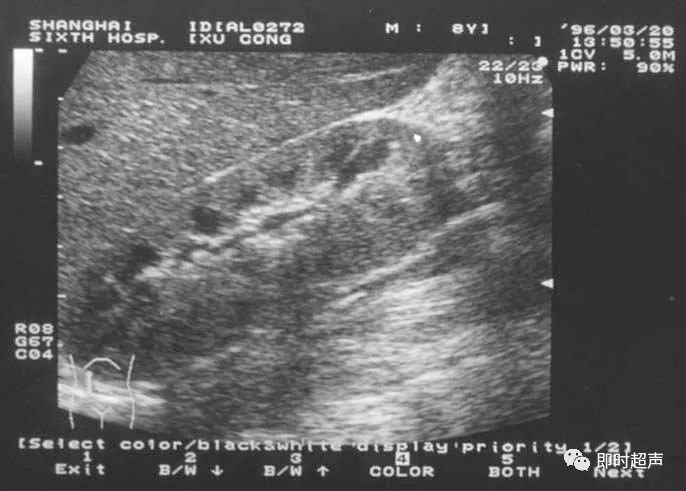

3.肾母细胞瘤(nephroblastoma)声像图

肾母细胞瘤又称Wilm’s瘤,是儿童的肾实质肿瘤,发现时往往已很大,侵占肾的大部。肿瘤有包膜回声,内部回声欠均匀或呈混合回声型。